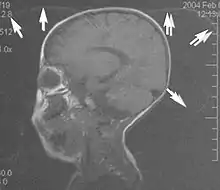

Motion artifacts

A motion artifact is one of the most common artifacts in MR imaging.[2] Motion can cause either ghost images or diffuse image noise in the phase-encoding direction. The reason for mainly affecting data sampling in the phase-encoding direction is the significant difference in the time of acquisition in the frequency- and phase-encoding directions.[1] Frequency-encoding sampling in all the rows of the matrix (128, 256 or 512) takes place during a single echo (milliseconds). Phase-encoded sampling takes several seconds, or even minutes, owing to the collection of all the k-space lines to enable Fourier analysis. Major physiological movements are of millisecond to seconds duration and thus too slow to affect frequency-encoded sampling, but they have a pronounced effect in the phase-encoding direction. Periodic movements such as cardiac movement and blood vessel or CSF pulsation cause ghost images, while non-periodic movement causes diffuse image noise (Fig. 1). Ghost image intensity increases with amplitude of movement and the signal intensity from the moving tissue. Several methods can be used to reduce motion artifacts, including patient immobilisation, cardiac and respiratory gating, signal suppression of the tissue causing the artifact, choosing the shorter dimension of the matrix as the phase-encoding direction, view-ordering or phase-reordering methods and swapping phase and frequency-encoding directions to move the artifact out of the field of interest.[1]